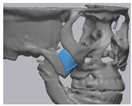

2.2. Computer-Aided Virtual Surgery, Design, and Fabrication of Patient-Specific Devices

2.3. Surgical Procedure